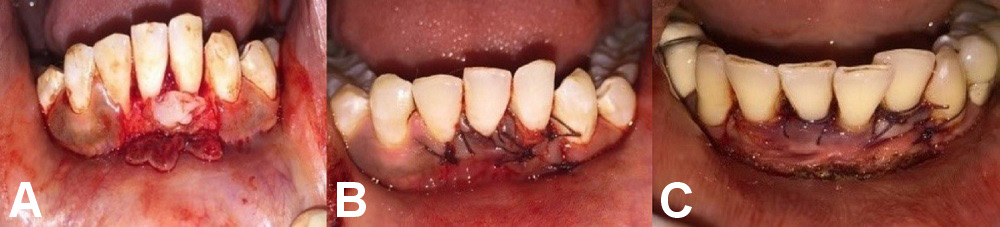

Group B comprised 12 patients who underwent laser-assisted RC by CAF and PRF application (Figure 3).

Group B

A similar surgical protocol was followed in group B, but an additional vestibular releasing incision was made using an optical-fiber diode laser at a power of 3 W in the continuous mode (Figure 5). This procedure helped prevent muscle reattachments that could hinder the outcome of the treatment. Photobiostimulation was performed at the end of the RC procedure and on day 7 with a 980 nm diode laser at a power of 1 W in the continuous mode for 60 s (Figure 6).